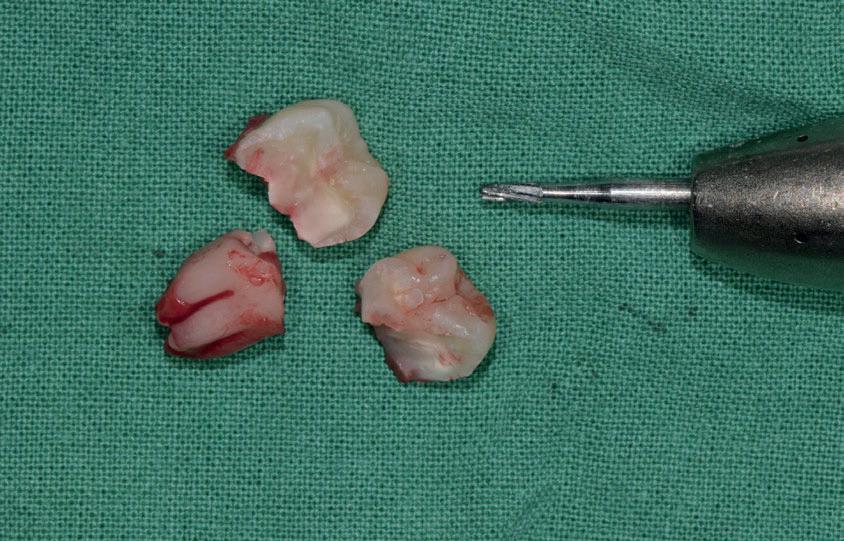

Questo è un paziente di 22 anni ed essendo un amico, ho potuto ben documentare il caso con il suo consenso: il suo dente del giudizio inferiore sinistro è stato estratto utilizzando il manipolo dritto. Figg. 143-149

Figg. 143-149 - Caso 1, paziente di 22 anni: tecnica di estrazione con divisione orizzontale utilizzando il manipolo dritto. Fig. 143 Fig. 144 Fig. 145 Fig. 146 Fig. 147 Fig. 148 Fig. 149

Il seguente caso chirurgico è di un 4.8 mesio-inclinato e parzialmente incluso. Dopo un’incisione a busta, il

dente è stato separato al centro per fare una coronectomia, prima della porzione distale e successivamente della porzione mesiale. Facendo leva quindi è stato possibile rimuovere le radici unite. Figg. 165-172

Abbiamo estratto il dente del giudizio inferiore di destra in una paziente di 22 anni, un’amica, utilizzando il manipolo dritto, con il proposito di fare delle foto dell’intervento. Figg. 173-179

Dalla radiografia (Fig. 166) sembrava che il dente avesse due radici separate, quindi è stato eseguito un taglio orizzontale utilizzando il manipolo dritto per sezionare il dente a metà. Tuttavia, la corona si è frat-

turata poiché in realtà le radici erano unite e il dente non è stato sezionato completamente.

Bisogna prendere in considerazione sempre molti fattori come, ad esempio, la forma delle radici, il sottosquadro nella regione distale del secondo molare e l’osso alveolare disto-vestibolare. Se necessario la corona e le radici vengono separate intenzionalmente per estrarre il dente, proprio come in questo caso.